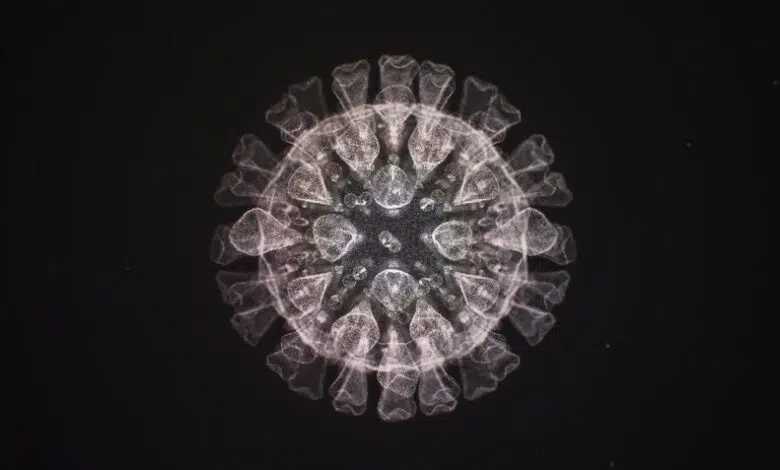

En el caso del SARS-CoV-2, las secuencias del genoma completo del virus de miles de pacientes nos permitieron buscar patrones convergentes. Si bien la mayoría de las mutaciones son únicas, algunas se vuelven más frecuentes a medida que el virus se replica con éxito e infecta a muchas personas. Si la misma parte del virus muta repetidamente y se vuelve más frecuente en diferentes muestras de todo el mundo, es probable que esa mutación codifique una adaptación que ayude al virus a reproducirse y propagarse.

Gracias a la vigilancia genómica mejorada de los coronavirus, varios estudios recientes han caracterizado la evolución convergente. En los EE. UU., nuestro laboratorio ha identificado al menos siete linajes genéticamente independientes que tienen una mutación en una ubicación específica en la infame proteína espiga del virus, que utiliza para fijarse en las células humanas. Spike tiene una serie de aminoácidos enlazados con una mutación en la posición 677. En el SARS-CoV-2 original, este era el aminoácido glutamina, abreviado Q.

En seis linajes, esta Q fue mutada a otro aminoácido, histidina (H), conocido como 677H. En el séptimo linaje, Q fue mutado a otro aminoácido, prolina (P). Cada linaje también tiene una mutación llamada S:614G, el primer cambio notable en el virus descubierto hace unos meses y tan extendido que ahora se encuentra en el 90 por ciento de todas las infecciones. Nombramos a los siete linajes estadounidenses en honor a aves comunes, como «petirrojos» y «pelícanos», para ayudarnos a distinguirlos y rastrearlos, y para evitar sesgos al nombrarlos según la región en la que fueron descubiertos por primera vez.

Bloodlines fuera de los EE. UU. también adquirió 677H, incluido un gran grupo en Egipto, Dinamarca, India y Macedonia. Una nueva variante llamada B.1.525 también tenía 677H, al igual que varios linajes de B.1.1.7, una de las primeras versiones preocupantes que se descubrió. La ocurrencia globalmente sincronizada de la mutación S:677 y su prevalencia quíntuple proporcionan una fuerte evidencia de que estos cambios deben mejorar de alguna manera la aptitud viral. Todavía no sabemos cómo, pero vale la pena señalar que S:677 limita con una región de la proteína espiga que ayuda al virus a ingresar e infectar las células humanas.

Este está lejos de ser el único ejemplo de convergencia de SARS-CoV-2. Las mutaciones en al menos ocho posiciones diferentes en la proteína del pico aumentaron simultáneamente en todo el mundo, ocurriendo en B.1.1.7 y otras variantes de gran interés, denominadas B.1.351, P.1 y P.3. Estas variantes comparten una combinación de mutaciones en las posiciones 18, 69-70, 417, 452, 501, 681 y una mutación E484K implicada específicamente en la evasión de anticuerpos neutralizantes. Por esta razón, estas mutaciones definidas y compartidas ahora se informan en dos de los principales sitios web científicos que rastrean variantes (http://covariants.org/ y http://outbreak.info) para simplificar y consolidar nuestra fuerza de atención. Los Centros para el Control de Enfermedades de EE. UU. y los medios de comunicación han tardado en centrarse en la importancia de estas mutaciones clave, pero eso está cambiando porque son estos cambios los que podrían alterar las funciones del virus, como su infectividad o su capacidad para evadir las vacunas.